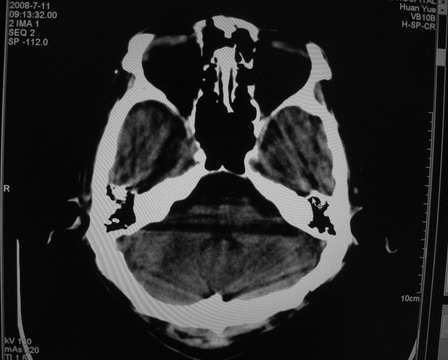

患者 男 69岁 头晕头痛不适

多发病灶,指状水肿,首先诊断转移瘤。

多个结节并周围大面积水肿区,多考虑多发性脑转移瘤

小病灶、大水肿,病灶多发,首先考虑多发转移瘤;建议查原发灶。

额顶叶多发小病灶、大水肿,首先考虑多发转移瘤;建议查原发灶

脑内多发病灶,小病灶,大水肿。

典型转移性肿瘤。

应进一步检查,查找原发病灶。

结果 : 该患者结肠癌病史5年 考虑脑转移